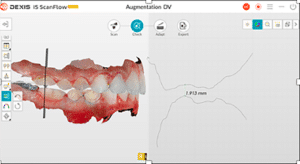

Lors de cette première consultation, en plus de l’examen clinique, on réalise une empreinte optique (Fig.2).

Fig.2.

Elle a deux buts. Le premier relève de la communication : il est plus facile pour la patiente de se rendre compte de l’état d’usure de ses dents avec une image 3D en plus des photographies et du miroir de courtoisie. Le deuxième but est l’analyse de l’occlusion. Grâce au logiciel d’exploitation (ici, Dexis IS Scan Flow), on se rend bien compte que l’occlusion est serrée avec des contacts extrêmement forts à droite (en rouge sur le Scan Flow). Il est alors facile de conclure et d’expliquer dès à présent à la patiente qu’il est impossible de restaurer son sourire dans cette situation occlusale. Pour redonner de la hauteur aux dents antérieures il faut de la place, créée soit par soustraction en préparant les dents antérieures, soit par addition en relevant la hauteur des dents postérieures. La patiente fait rapidement son choix. Pour nous, cela signifie qu’il va falloir augmenter la DVO.